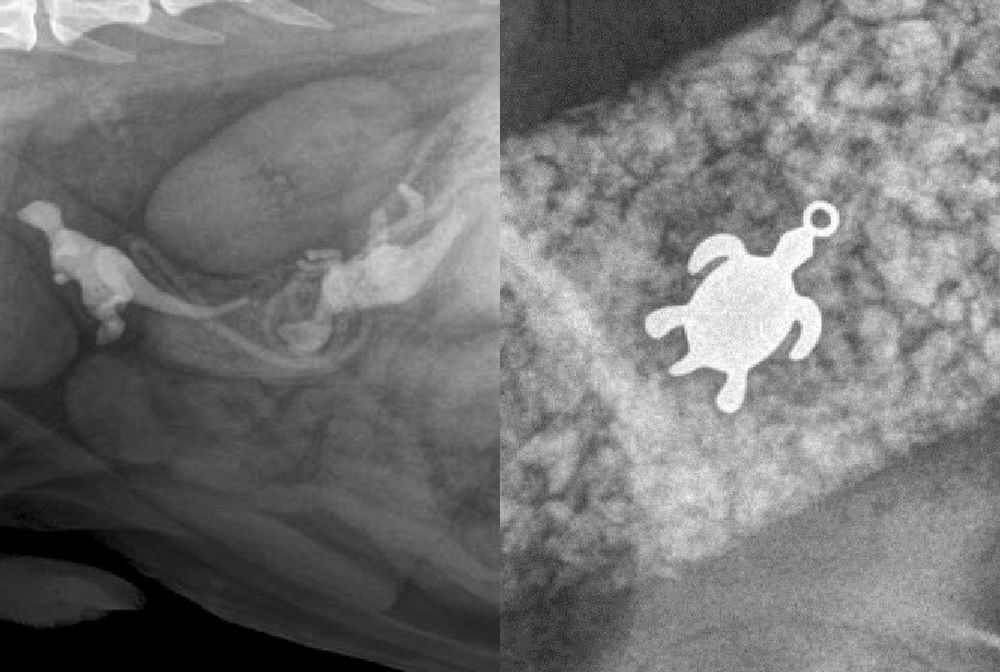

/ 11Żółwik

Obraz

© Veterinary Practice News / Don Harris, DVM, of Avian & Exotic AMC in Miami

Drugie miejsce należy do Loli, 7-kilogramowej żółwicy. Z przedłużającym się brakiem apetytu trafiła do weterynarza, a ten na zdjęciu rentgenowskim odkrył źródło problemu - połknięty wisiorek z... żółwiem wielkości 15 mm. Po operacji Lola wróciła w pełni do zdrowia.